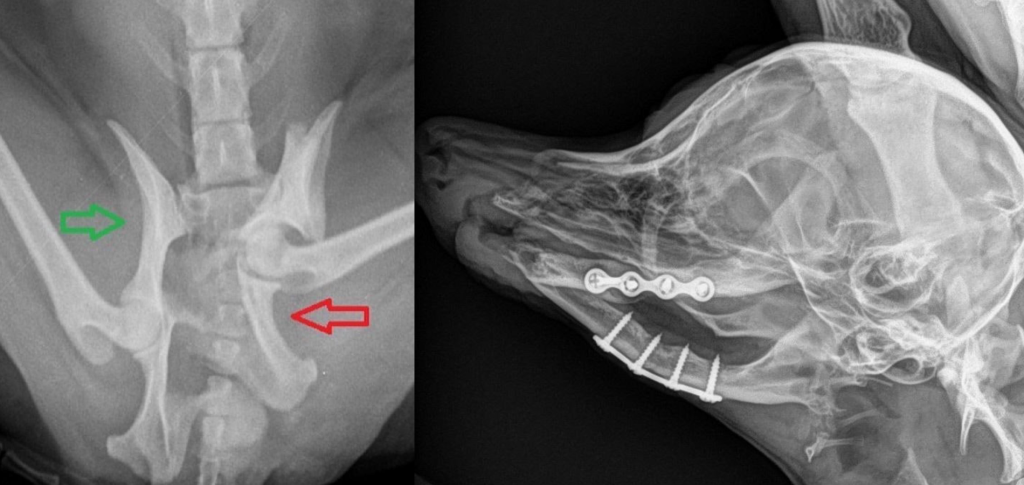

(Переломы таза и челюсти у собак после автотравмы)